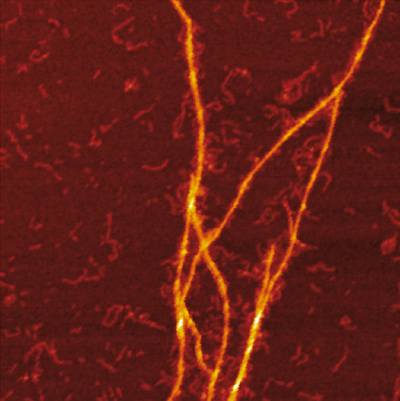

Deciphering the interactions between proinflammatory S100A9 protein and Aβ42 peptide in Alzheimer’s disease is fundamental since inflammation plays a central role in the disease onset. Here the researchers used charge detection mass spectrometry (CDMS) together with biophysical techniques to provide mechanistic insight into the co-aggregation process and differentiate amyloid complexes at a single particle level. Combination of mass and charge distributions of amyloids together with reconstruction of the differences between them and detailed microscopy reveals that co-aggregation involves templating of S100A9 fibrils on the surface of Aβ42 amyloids. Kinetic analysis further corroborates that the surfaces available for the Aβ42 secondary nucleation are diminished due to coating by S100A9 amyloids, while the binding of S100A9 to Aβ42 fibrils is validated by a microfluidic assay. The researchers demonstrate that synergy between CDMS, microscopy, kinetic and microfluidic analyses opens new directions in interdisciplinary research.